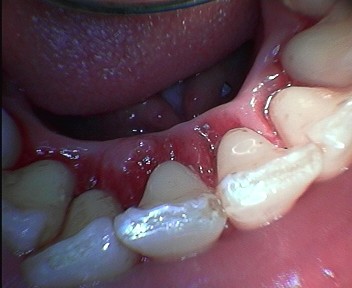

Magas színvonalú fogászati ellátás Sopron belvárosában, több mint 30 év szakmai tapasztalatával Dr. Kiss Tamás várja pácienseit.

Modern fogászati rendelőnk teljes körű fogászati ellátást biztosít pácienseink számára. Korszerű eszközökkel és fájdalommentes kezelésekkel gondoskodunk a szép és egészséges mosolyról.

Magas színvonalú fogászati ellátás

Több mint 30 év szakmai tapasztalat